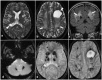

Labrune syndrome is a rare neurological disorder, with less than 100 reported cases since its identification. This disorder causes progressive cerebral degeneration. This case report describes a 21-year-old male patient who presented with tonic-clonic seizures. Upon examination, he was found to have symmetrical dense calcifications in the bilateral basal ganglia, thalami, and dentate nuclei, as well as in the white matter of both hemispheres, accompanied by cysts. MRI brain revealed confluent areas of T2/FLAIR hyperintensities involving the deep periventricular white matter in both cerebral hemispheres with sparing of subcortical U-fibres and two cysts in the left frontal and right posterior temporal region. No serologic evidence of a parasitic infection was found. Treatment was directed at addressing symptoms, and surgery was not required as the cysts were not causing a mass effect. The condition is the result of an autosomal mutation in the SNORD118 gene, a non-protein encoding gene that mediates rRNA synthesis.